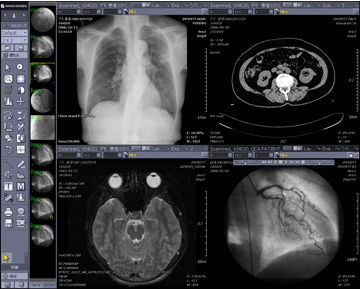

ハンギングプロトコルとは,ユーザーの読影目的に合わせ,画面構成をカスタマイズする機能のことです。モダリティや検査部位,ツールバー,サムネイルまで画面構成を設定することが可能です。過去画像比較(図4)や縦隔・肺野比較(図5),マルチモダリティ表示(図6)や3D画像作成機能(図7)までもがワンクリックで意図した画面レイアウトで表示され,迅速で簡単な読影環境を提供します。ハンギングプロトコルの設定は,ユーザーごとの設定であるため,ハンギングプロトコルをフル活用することにより,自分だけのオーダメイドPACSとして使用することができます。

![]() 図6 マルチモダリティ表示 |

![]() 図7 3D画像作成 脳血管抽出 |